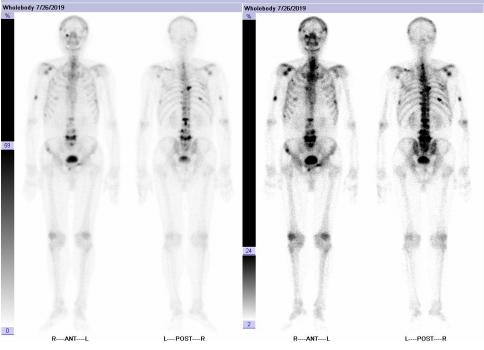

全身骨显像:肿瘤多发骨转移。

图2 患者起始治疗前全身骨显像